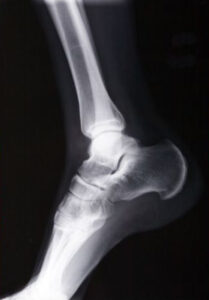

X-ray Services

Broke or dislocated a bone? We will bring our x-ray machines to your location to take x-rays of your injury.